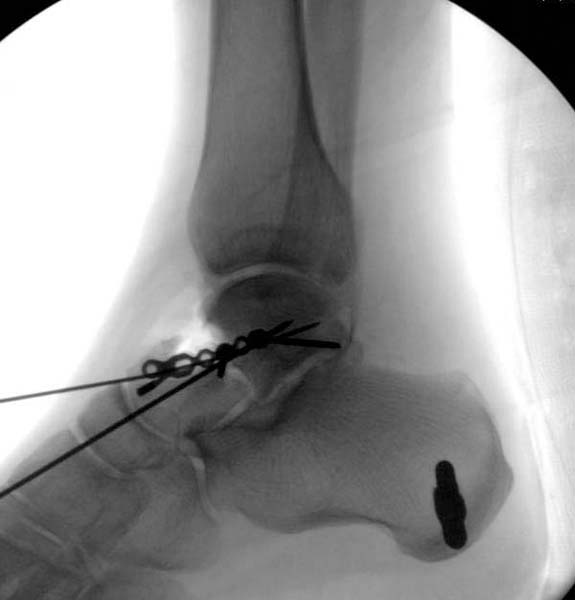

Больная стабильная после хирургических мероприятии и получив добро, приступили к закрытому вправлению таранной кости с укладкой наружного фиксатора. Затем укладка больную на бок и открытый остеосинтез перелома-вывиха головки бедра.

По характеру повреждения головка находится сзади и напрашивается задний Кохер-Лангенбек доступ, но в заднем доступе имеется риск повреждения магистрального кровоснабжения головки a. circumflexa. Более щадящая trochanteric flip (digastric osteotomy) сохранит кровоснабжение и дасть возможность работу при вывихнутом суставе.

После спадения отека на стопе произведена фиксация тарана. Кстати, коллеги пересмотрели первоначальную консультацию по позвоночнику и на двух уровнях провели фиксацию. Из-за длительного постельного режима без нагрузки таз не стали оперировать...